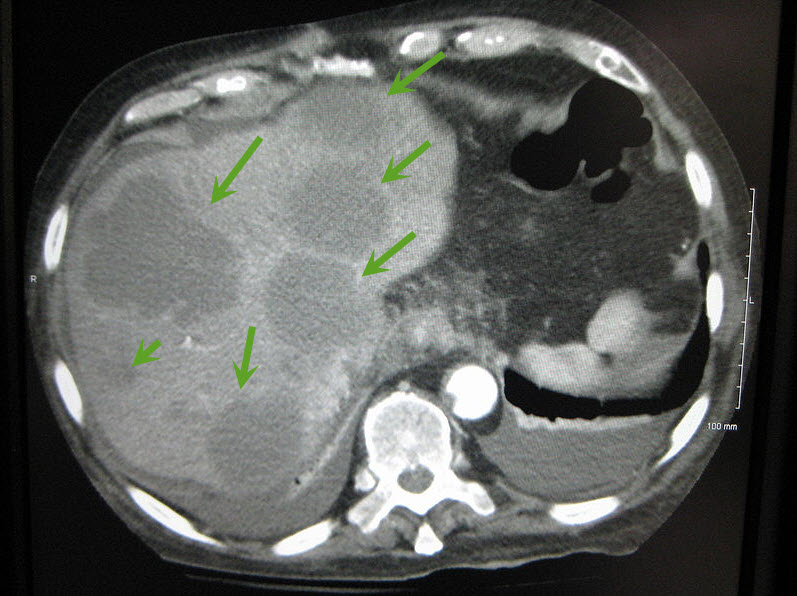

| Axial CT of the abdomen showing multiple liver metastases. Image courtesy of James Heilman, MD / Wikimedia Commons / CC-BY-SA-3.0 |